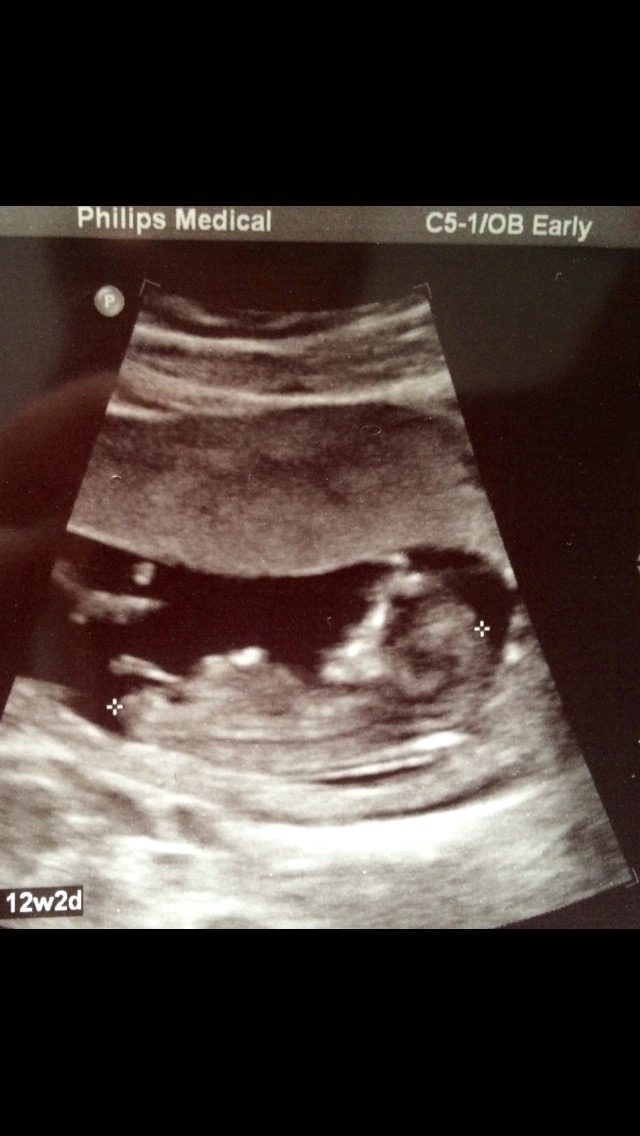

Girl or boy... what do you think? Help!!

12 w 2 d... what do you think?